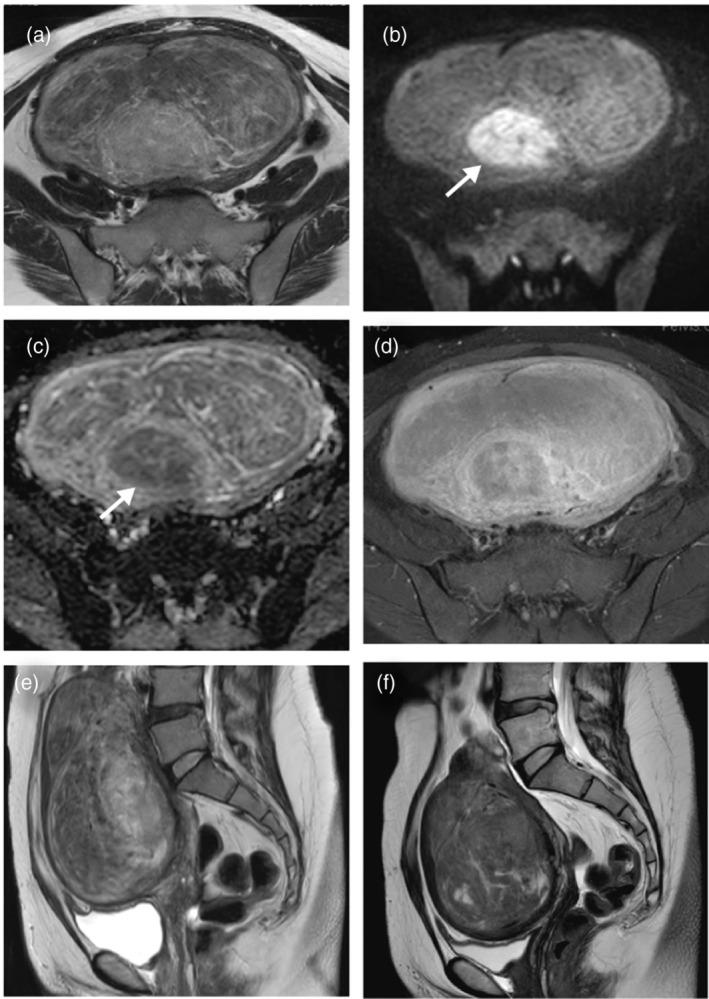

Large uterine fibroids that grow rapidly over a short period should be differentiated from uterine leiomyosarcoma, and their treatment remains controversial in women seeking to conceive. Here, we report two cases of uterine fibroids treated with short-term relugolix administration followed by myomectomy. Needle biopsy specimens obtained before relugolix administration showed no malignancy, and significant tumor shrinkage was observed following treatment. Both patients subsequently underwent myomectomy. One patient achieved a live birth 14 months after myomectomy, whereas the other experienced improvement in severe anemia, allowing her to prepare for pregnancy. Histological examination after relugolix administration revealed atrophic changes in spindle cells within the fibroids, characterized by nuclear crowding and decreased immunoreactivity for desmin and α-smooth muscle actin. The significant fibroid shrinkage observed after the short-term administration of relugolix provided a rationale for myomectomy, improved anemia, and facilitated appropriate uterine reconstruction, ensuring structural integrity for future pregnancies in women of reproductive age.

摘要

短期内迅速生长的大型子宫肌瘤应与子宫平滑肌肉瘤相鉴别,对于有生育需求的女性,其治疗方案仍存在争议。在此,我们报告两例子宫肌瘤患者,先接受短期瑞卢戈利治疗,随后进行肌瘤切除术。在给予瑞卢戈利之前获取的穿刺活检标本未显示恶性特征,治疗后观察到肿瘤显著缩小。两名患者随后均接受了肌瘤切除术。一名患者在肌瘤切除术后14个月成功分娩,而另一名患者的严重贫血状况得到改善,使其能够为妊娠做准备。给予瑞卢戈利后的组织学检查显示肌瘤内梭形细胞出现萎缩性改变,其特征为核拥挤以及结蛋白和α平滑肌肌动蛋白的免疫反应性降低。短期给予瑞卢戈利后观察到的肌瘤显著缩小为肌瘤切除术提供了理论依据,改善了贫血状况,并有助于进行适当的子宫重建,确保育龄期女性未来妊娠时子宫结构的完整性。